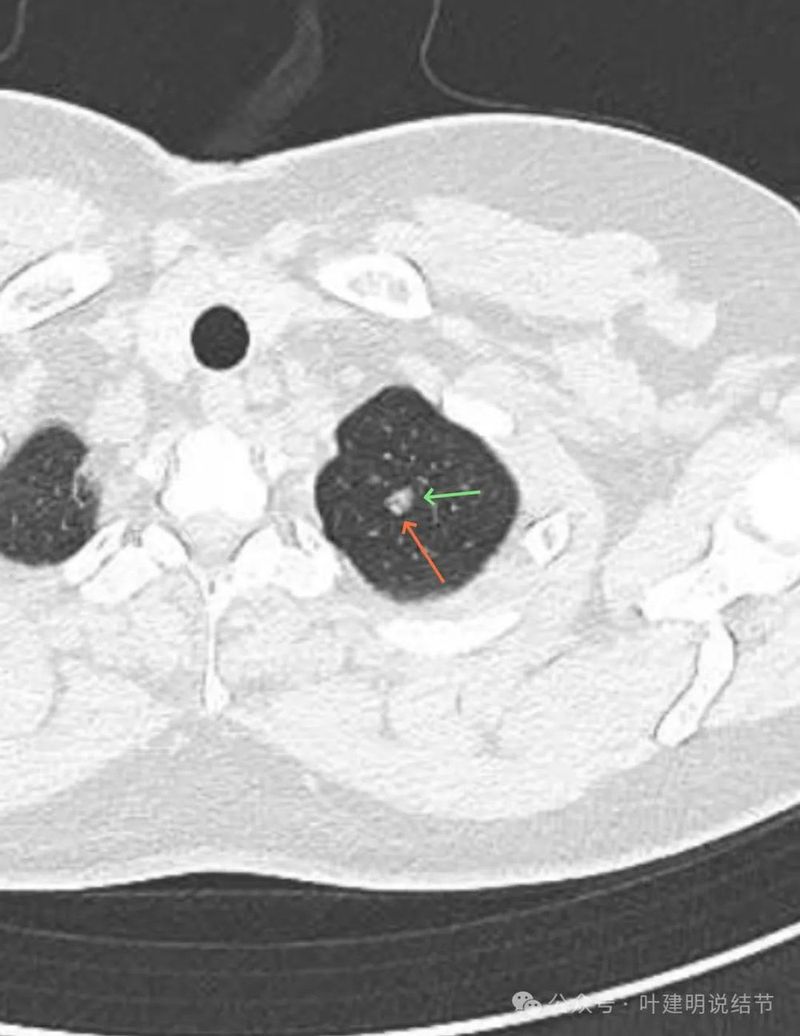

有明显磨玻璃成分,有血管紧贴,有小血管穿行,整体轮廓与边界清。